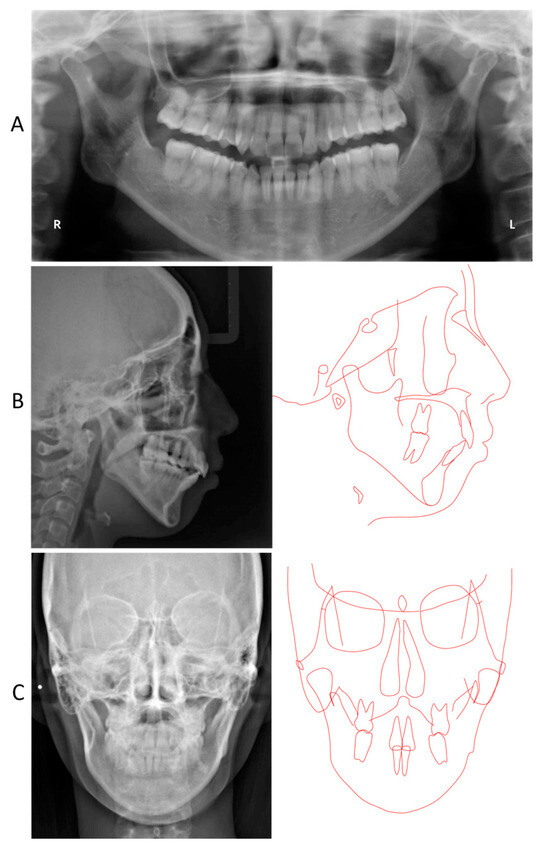

2. Detailed Case Description

2.4. Treatment Results